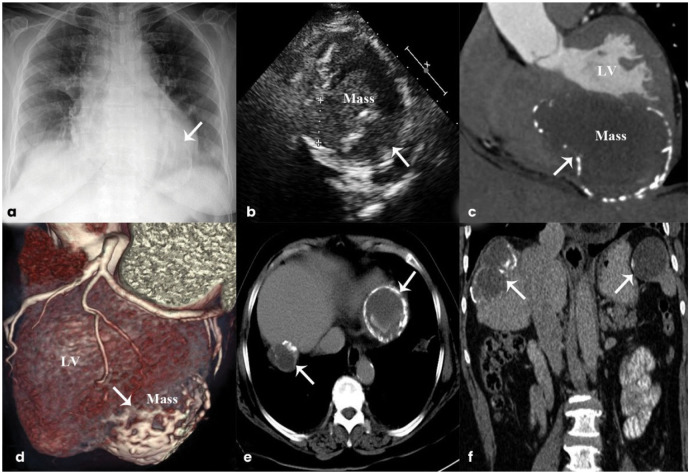

Multimodality Imaging Assessment of a Multi-Organ Hydatid Cyst